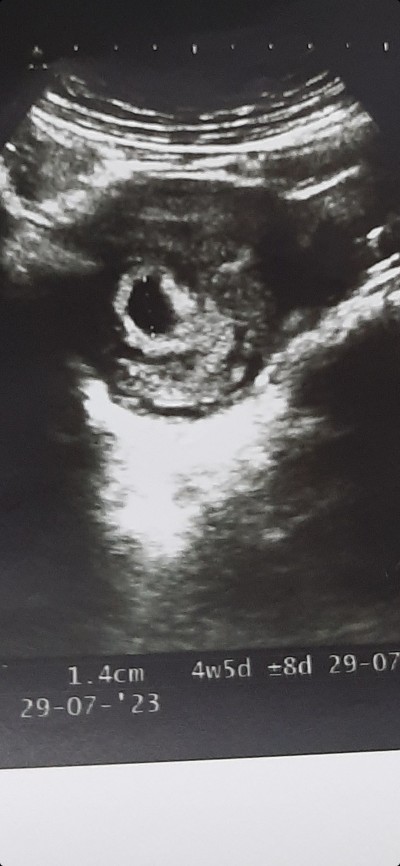

6+2 tek yumurta ikizi gebelik

6+2 tek yumurta ikizi olduğunu öğrendim yanlız bebekler arasında ayrılması gereken zar görünmedi doktor yapışık ikiz olabilir dedi böyle bir durumla karşılaşan var mı acaba sonradan aradaki zar görünür mü ?

İkiz gebelik

Benimki de 4

hafta 5 günlük